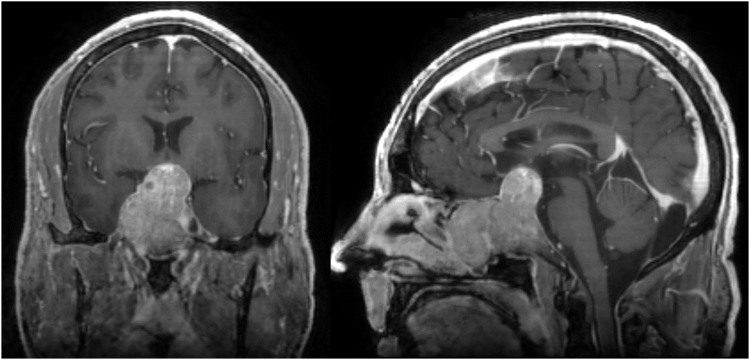

A 54-year-old man presented with gradually worsening vision over 1 year. Magnetic resonance imaging demonstrated a 5.2-cm sellar and suprasellar mass with cavernous sinus invasion, mass effect on the optic chiasm, and extension into the sphenoid sinus, nasal cavity, and clivus. Preoperative workup was remarkable for erythrocytosis without sleep apnea and increased levels of follicle-stimulating hormone (FSH), luteinizing hormone (LH), prolactin, and testosterone. Immunohistochemistry results following endoscopic transsphenoidal resection confirmed dominant staining for steroidogenic factor-1, FSH, and LH. Postoperatively, the patient’s FSH level decreased, whereas the LH level normalized within 1 week. The free testosterone level normalized at 9 months. The patient underwent radiotherapy for a small amount of residual tumor in the right cavernous sinus and has demonstrated no evidence of disease or hormonal progression.